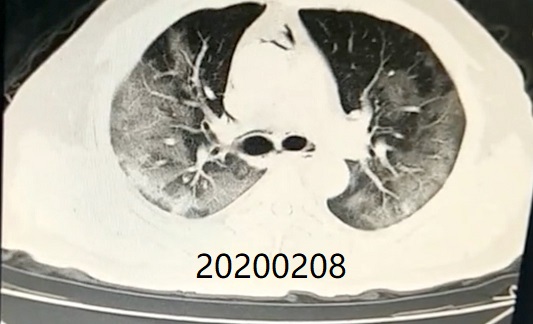

Comparison of CT imaging of chest before and after treatment with the patient (Mr. Zhang)